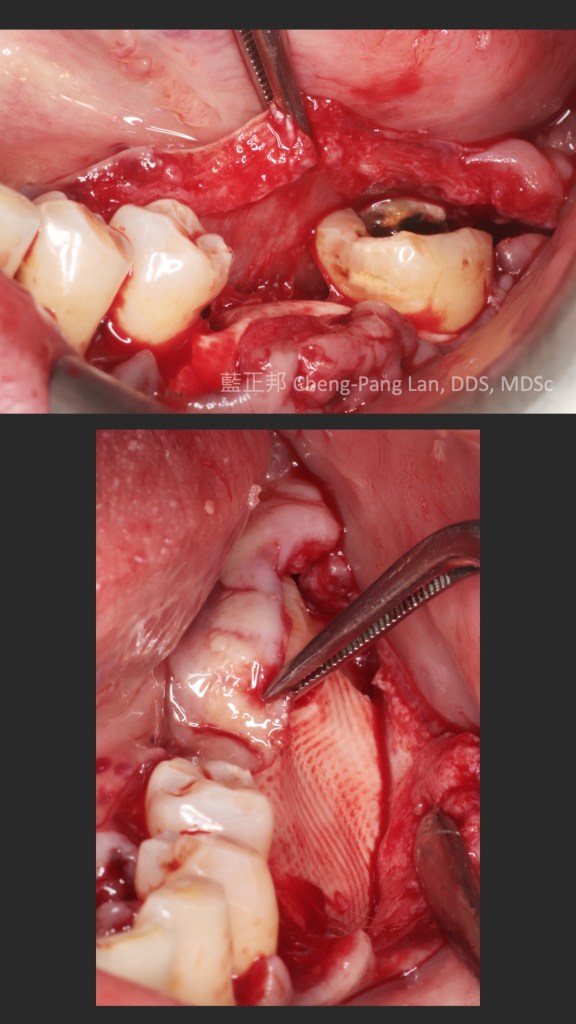

這個案例,最早沒把握能救回來,但是做完非手術治療,發現恢復非常好。

於是大膽地請矯正與假牙專科醫師一起幫忙完成。其實病人本身也同意,若途中狀況不好,還是得拔除。我知道這種案例,其實對其他專科來說,可能是有壓力的,不容易處理,也是難症。

好佳在,兩位神隊友都完成了,非常感謝合作專科的信任,還有,病患六年來維持得非常好,目前囊袋正常、零出血、零發炎。

回頭看,一開始就拔掉牙齒,改走其他路線,或許也可以,每位醫師選擇的或許不一樣,並沒有標準答案。

但是,能幫病患留下自己的牙齒,真的是很開心的一件事~~